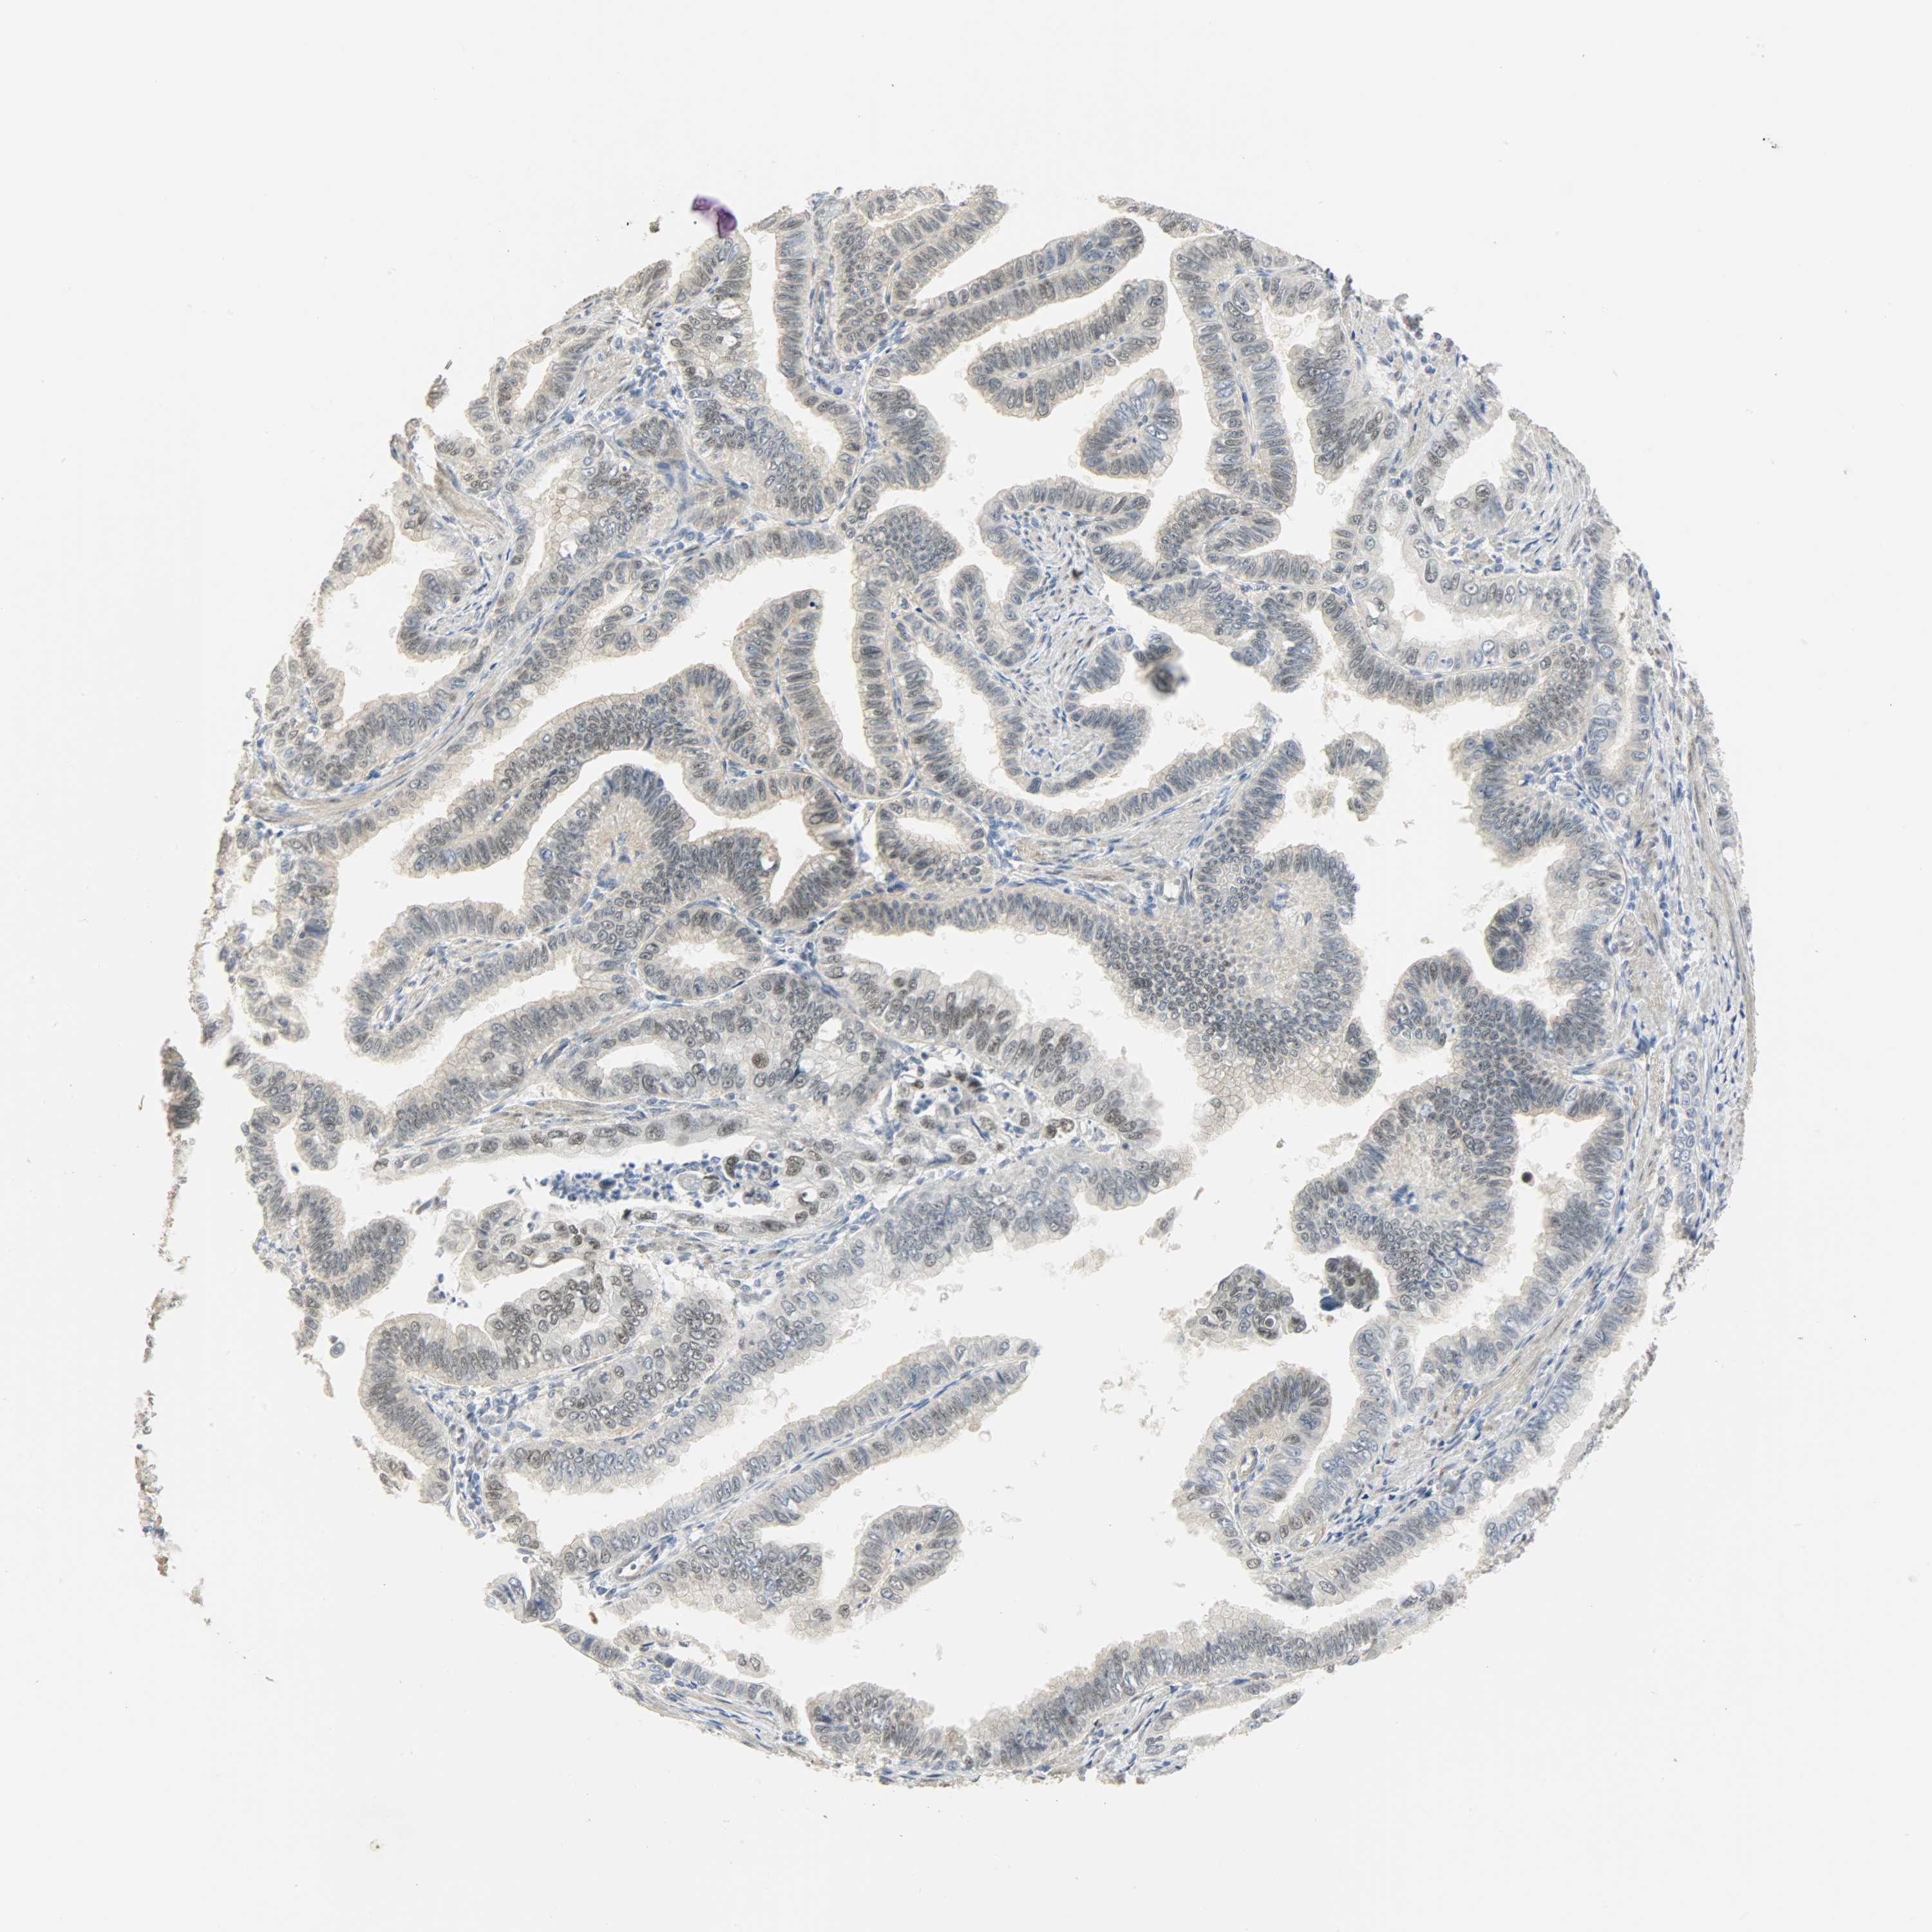

PANCREATIC CANCER - Protein expressioni

A mouse-over function shows sample information and annotation data. Click on an image to view it in a full screen mode. Samples can be filtered based on level of antibody staining by selecting one or several of the following categories: high, medium, low and not detected. The assay and annotation is described here.

Note that samples used for immunohistochemistry by the Human Protein Atlas do not correspond to samples in the TCGA dataset.

Antibody stainingi

Antibody staining in the annotated cell types in the current human tissue is reported as not detected, low, medium, or high, based on conventional immunohistochemistry profiling in selected tissues. This score is based on the combination of the staining intensity and fraction of stained cells.

Each image is clickable and will lead to virtual microscopy that enables deeper exploration of all samples and also displays staining intensity scores, fraction scores and subcellular localization as well as patient and tissue information for each sample.

Antibody HPA036356

Antibody CAB004986

Antibody CAB017025

Adenocarcinoma, NOS

Adenocarcinoma, metastatic, NOS